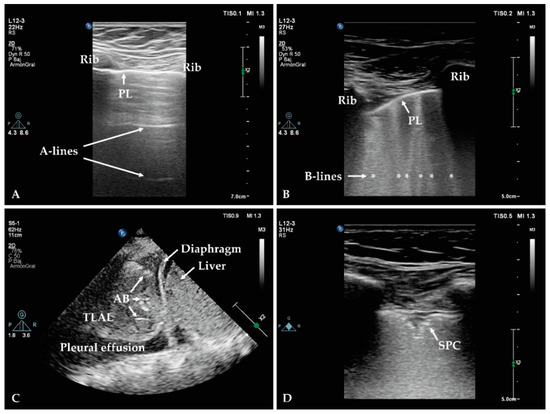

2.1.2. Lung Ultrasound